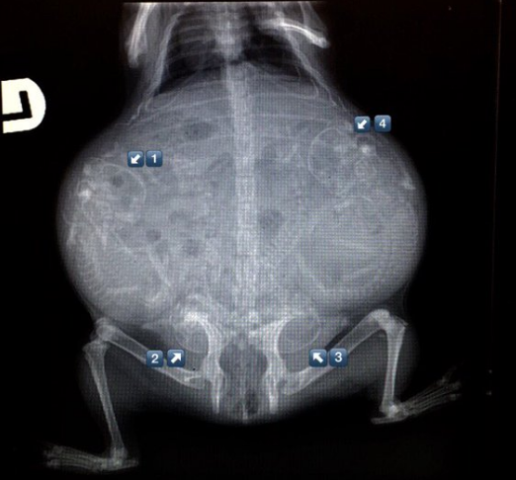

Մենք բոլորս լավ պատկերացնում ենք, թե ինչպես է անցնում մարդու հղիությունը, և շնորհիվ ժամանակակից տեխնոլոգիաների՝ կարող ենք տեսնել երեխային մայրիկի արգանդում հղիության ամենավաղ փուլում։ Իսկ ինչպե՞ս է ընթանում կենդանիների հղիությունը։ Մասնագետները, ովքեր հոգ են տանում հղի կենդանիների մասին, ներկայացրել են նրանց ռենտգենային և ուլտրաձայնային լուսանկարները, որոնք ձեր դատին է հանձնում «twizz.ru» կայքը։

Շուն